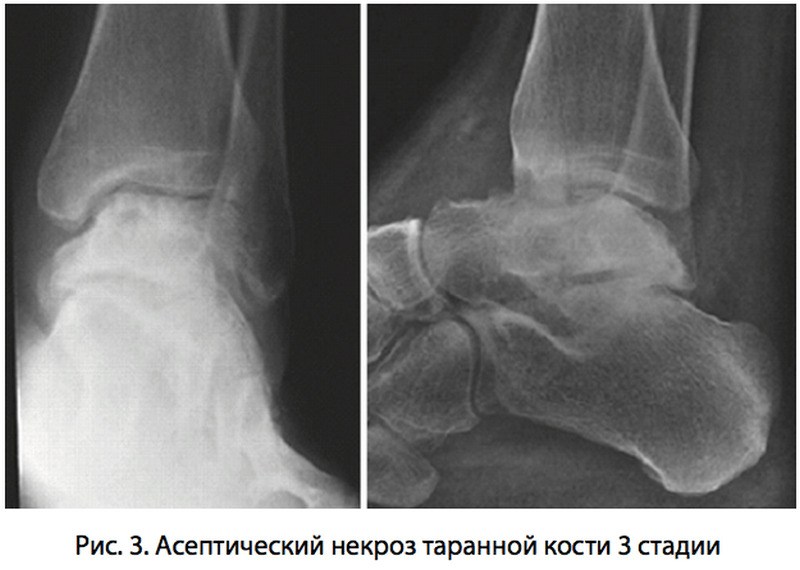

В клинической практике принято выделять несколько стадий изменений таранной кости при аваскулярном некрозе:

- первая стадия характеризуется функциональными нарушениями кровообращения в костной ткани и не имеет признаков органических повреждений кости;

- сохранение нарушения кровотока в области таранной кости приводит к развитию склероза под надкостницей и появлению кист, которые соответствуют областям некроза костной ткани;

- третья стадия, наблюдаемая при значительных изменениях в кости, проявляется деформацией костной ткани с развитием поднадкостничного коллапса;

- четвертая, или терминальная стадия патологии характеризуется выраженной деформацией кости, разрушением хрящевых поверхностей, образованием больших полостей внутри костной ткани. Как правило, подобные изменения полностью необратимы.

Основная задача врачей – выявить заболевание на начальных стадиях его развития, не допустив дегенеративных изменений в кости с ее деформацией.